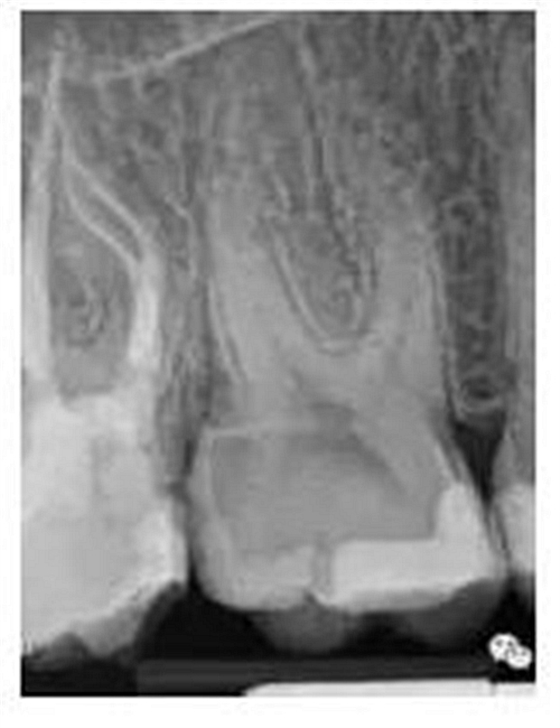

最后來玩一個根管治療質(zhì)量的評估——下圖是武大彭彬教授的一個病例,仔細觀察可以挑出一點問題,但問題事出有因!看看你的“眼力”如何——問題在那里?教授的專業(yè)水平是不用懷疑的,那么事出的原因可能是什么?

問題答案:這個病例的問題主要反應在開髓的洞形修整,注意觀察該牙X-RAY的左側(cè)洞壁,如果常規(guī)情況制備成這樣是由于裂鉆破壞了洞壁和洞底所形成的臺階。如果評估根管治療的質(zhì)量那是要扣分的!但這個病例仔細觀察洞壁形態(tài)就可以看出:該病例屬于再治療的病例,因此還是屬于一個理想的病例。